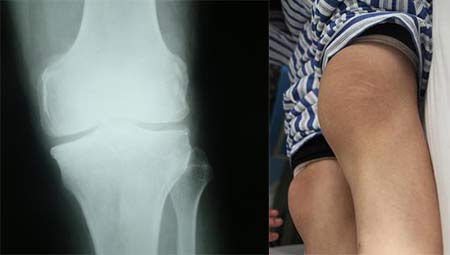

(图:陈先生膝关节X线片显示关节肿大,关节间隙变窄)

体检:面色苍白,腰背、膝关节压痛明显,膝关节红肿发热,穿衣不适

X线示:多处软骨组织破坏,关节畸形明显狭窄。